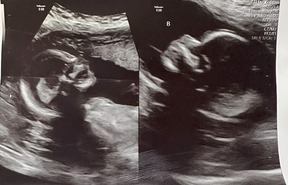

When Kelsey Hatcher visited her obstetrician for an ultrasound this year, she smiled when an image of a healthy fetus appeared on the screen.

Before leaving, Hatcher asked the nurse for further examination. Hatcher had been born with a second uterus, and she wanted the nurse to check on the health of that one, too.

The nurse at the University of Alabama at Birmingham’s hospital spread gel on the opposite side of Hatcher’s abdomen and went over it with the wand. They couldn’t believe what they saw on the screen.

Another fetus was growing in Hatcher’s second uterus. One in 1 million women become pregnant with two fetuses in separate uteruses, according to Richard Davis, a maternal-fetal medicine specialist treating Hatcher.

When she was eight weeks pregnant in May, Hatcher went to her first ultrasound appointment at the hospital. Hatcher was relieved when the nurse initially found only one fetus in her right uterus. But when the nurse looked at the left one, she discovered the twin.

Hatcher said she couldn’t believe the news and started laughing. The nurse called obstetrician Shweta Patel, who reviewed the images multiple times until she became certain there was a fetus in each of Hatcher’s uteruses.

Patel said that many women with two uteruses have only one fully developed and functional uterus. She said Hatcher’s eggs likely travelled through separate fallopian tubes and into the different uteruses.